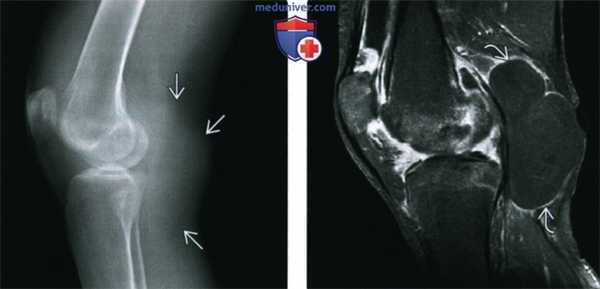

(Слева) Рентгенография в ПЗ проекции: позвоночник пациента с ХРА. Ранняя паравертебральная оссификация начинается от тела позвонка на некотором удалении от замыкательной пластинки и распространяется в направлении тела прилежащего позвонка, чем отличается от синдесмофита.

(Справа) Рентгенография грудопоясничного перехода в ПЗ проекции: типичные для этого заболевания зрелая оссификация и несколько асимметричное формирование синдесмофитов у мужчины 48 лет. (Слева) МРТ, сагиттальная проекция, режим TV. мостовидные синдесмофиты, некоторые из которых содержат костный мозг (тот же случай). Обратите внимание на изменения Романуса в углах тел позвонков, характеризующиеся сигналом высокой интенсивности. Эти изменения с сигналом высокой интенсивности в режиме Т1 указывают на хронический характер процесса, когда происходит жировое замещение в зонах имевшегося воспаления. В активную фазу воспаления в режиме Т1 был бы получен сигнал низкой интенсивности, однако в режиме Т2 сигнал был бы гиперинтенсивным.

(Справа) МРТ, сагиттальная проекция, режим Т2: также визуализируются изменения Романуса и костный мозг в синдесмофите, поскольку в этой последовательности режим подавления жира не применялся. (Слева) КТ, аксиальная проекция, костный режим: начальные, еще слабовыраженные изменения аксиального скелета с ранними эрозиями крестцово-подвздошного сустава и легким сопутствующим склерозом. Изменения были в большей степени выражены справа, чем слева; пациенту был установлен диагноз ХРА.

(Справа) Рентгенография в ПЗ проекции: двухстороннее, но асимметричное поражение крестцово-подвздошных суставов со склерозом. Слева изменения более выражены, чем справа.